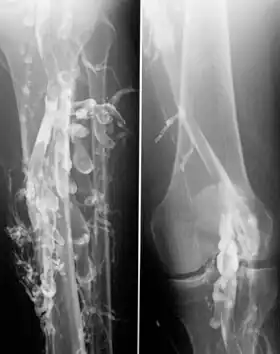

Venography in a patient with deep vein thrombosis

Contrast venography is the gold standard for judging diagnostic imaging methods for deep vein thrombosis; although, because of its cost, invasiveness, and other limitations this test is rarely performed.[1]

Venography can also be used to distinguish blood clots from obstructions in the veins, to evaluate congenital vein problems, to see how the deep leg vein valves are working, or to identify a vein for arterial bypass grafting.